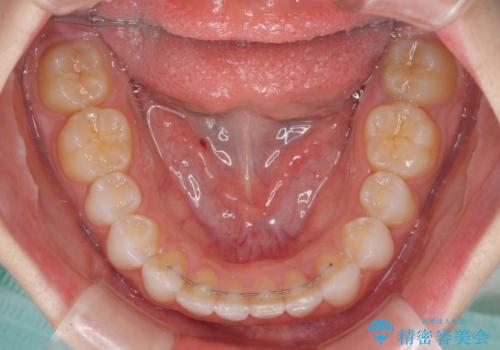

デコボコと深い咬み合わせの改善 インビザラインによる矯正治療

- 口元のデコボコと深い咬み合わせ(ディープバイト)を気にして来院された患者様です。

インビザラインによる上下歯列の拡大と、IPR(歯と歯の間を削る)にるスペースの獲得により、口元のデコボコとディープバイトを改善することとしました。

インビザラインは、装着していない時間がどれだけ短いかが、治療期間を大きく左右します。こちらの患者様は1日22時間以上、毎日欠かさず装着してくださったため、1年強という短期間で満足のいく歯列に整えることができました。